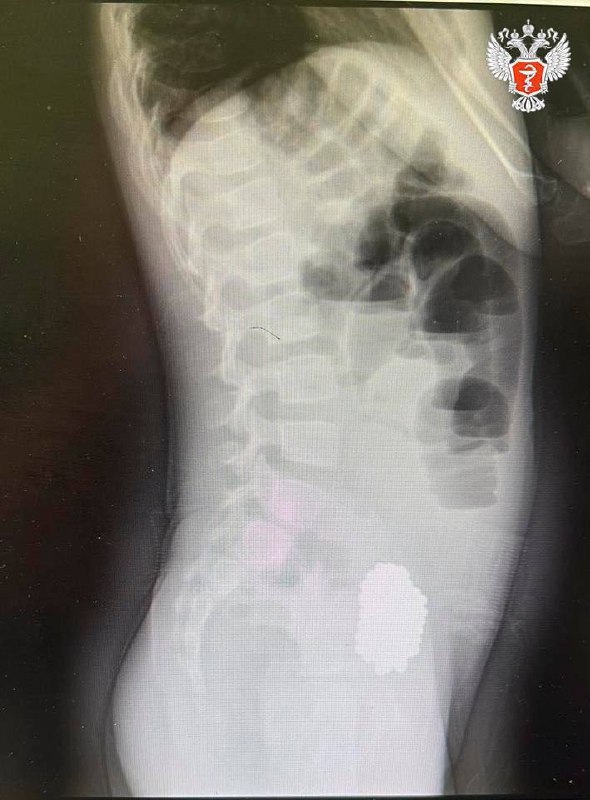

Девочку экстренно доставили в Клиническую больницу скорой помощи №7. При обследовании врачи диагностировали кишечную непроходимость, вызванную инородным телом. Рентгеновское исследование показало скопление слипшихся магнитных шариков, которые сдавливали стенки кишечника.